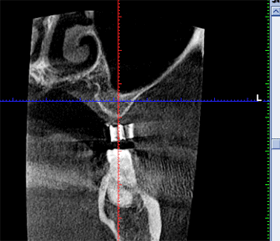

CT検査から内側に骨があることがわかりました。 |

内側の骨を利用し傾斜埋入をおこない、骨造成を回避できました。 |